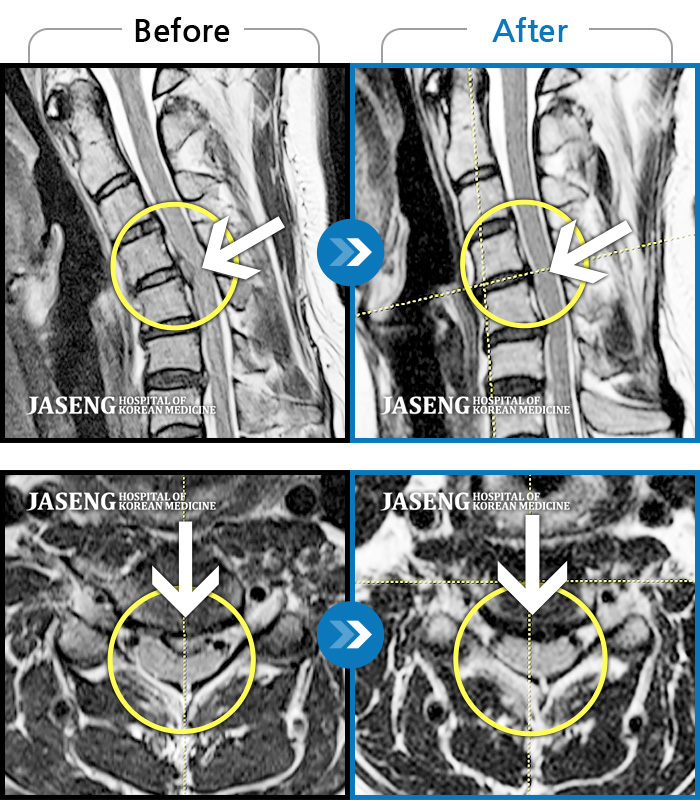

MRI 치료사례

날개뼈 안쪽의 통증으로 잠을 못 자고 양쪽 손(엄지)의 저림이 심해요.